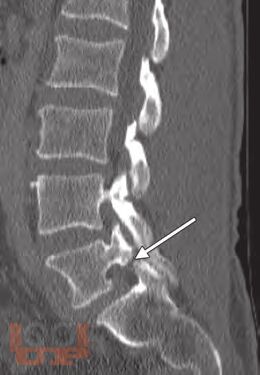

This is a unique atlas with contributions from international experts describing the most simple and advanced pain intervention techniques in a stepwise manner. The atlas provides a clear guide to identify the bony structures as seen on fluoroscopic examination enabling the operator to perform the spinal interventions safely. Remember: Bone is our Eye and Friend when performing spinal interventions under fluoroscopy. Chapters are consistently designedcovering indications, contraindications, equipment needed, and procedural stepswith the text presented in a bulleted style. Including several cases in some of the spinal intervention chapters will prepare the readers to overcome the challenges and the variability that are encountered in clinical practice. Some of the ultrasound-guided techniques described will enable readers to consider performing some pain-relief procedures in remote settings where fluoroscopy or CT guidance is not available.